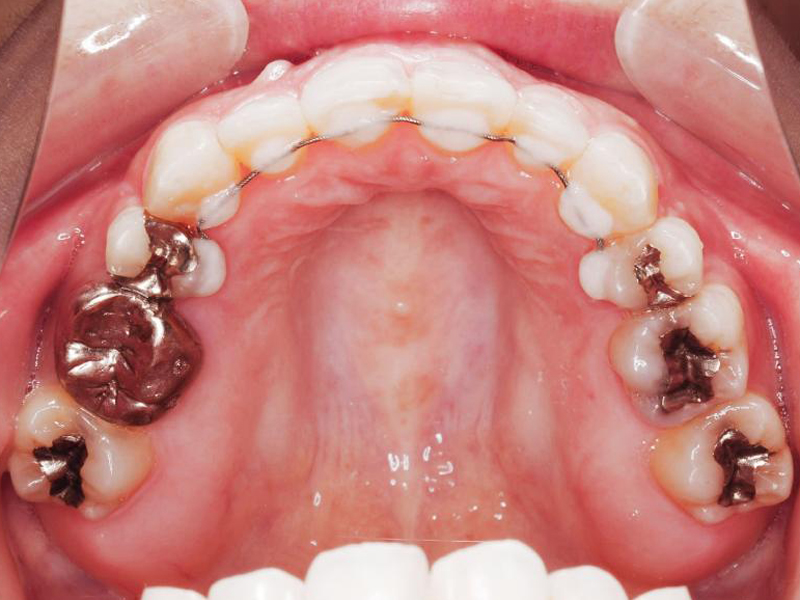

初診時の状態です。

治療経過 上顎

治療経過1 上顎

治療経過2 上顎

治療経過3 上顎

治療経過4 上顎

治療後 上顎